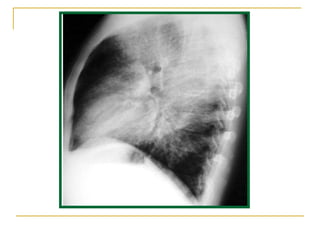

Neumonía por  P. Carinii  en paciente VIH

Paciente VIH positivo con neumonía por  Pneumocytis carinii  (fase subaguda o en resolución)

Neumonía por  Pneumocystitis carinii.  Patrón pulmonar intersticial bilateral.